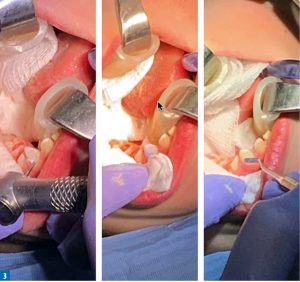

STRESZCZENIE: Leczenie zachowawcze zębów mlecznych nie jest łatwym zadaniem nie tylko ze względu na różnice w budowie mlecznego uzębienia w porównaniu ze stałym, ale przede wszystkim na utrudnioną współpracę z małoletnim pacjentem. W pracy przedstawiono trudności w leczeniu dzieci w gabinecie stomatologicznym, możliwe metody pracy oraz zalecane materiały odtwórcze. Opisano również przypadek kompleksowego leczenia trudnego pacjenta z zastosowaniem znieczulenia ogólnego.

SUMMARY: The conservative treatment of milk teeth is not an easy task, not only because of the differences in the structure of milk teeth compared to permanent, but, above all, a difficult cooperation with an underage patient. The paper presents difficulties in treating children in a dental office, possible work methods and recommended restorative materials. A case of the comprehensive treatment of a difficult patient with the use of general anaesthesia is also described.